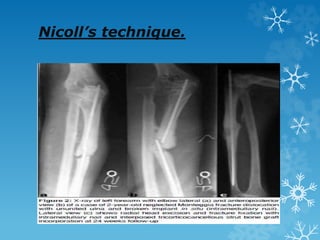

Nicoll’s technique.

 Blocks of the corticocancellous bone with a single cortex

from the iliac crest, augmented with rigid plate fixation

under compression.

 Good results using an Iliac crest graft with medullary

nail fixation using a hun (hunec) nail.

 Bones with segmental bone defects treated by

tricorticocancellous bone graft under optimum

compression with intramedullary fixation.

 The mean intercalary defect was 4.7 cm (range, 1.5–7.5

cm) after debridement.

 Authors have modified the Nicoll technique and used

tricorticocancellous bone strut, to fill the bone gap,

instead of wholly cancellous inserts.

 A tricorticocancellous iliac crest bone block, 2–3 mm longer

than the measured gap, was harvested. The width of the

graft was 2–2.5 cm.

 A square nail of predetermined size was negotiated in one

of the fragments and was protruded through the fracture

surface.

 The prepared strut (corticocancellous bone block) was

threaded over the nail and rotated, as per local geometry of

the bone and while maintaining sufficient traction, the strut

was reduced between the fragments and the nail was driven

further across the strut into the other fragment.

 Traction was then left which locked the corticocancellous

block under optimum compression over a nail between the

two fragments.

 Osteoperiosteal flaps were then raised on both bone host

graft junctions and cancellous chips were impacted all

around.

Nicoll’s technique.  Blocksof the corticocancellous bone with a single cortex from the iliac crest, augmented with rigid plate fixation under compression.  Good results using an Iliac crest graft with medullary nail fixation using a hun (hunec) nail.  Bones with segmental bone defects treated by tricorticocancellous bone graft under optimum compression with intramedullary fixation.  The mean intercalary defect was 4.7 cm (range, 1.5–7.5 cm) after debridement.  Authors have modified the Nicoll technique and used tricorticocancellous bone strut, to fill the bone gap, instead of wholly cancellous inserts.

Nicoll’s technique.  Atricorticocancellous iliac crest bone block, 2–3 mm longer than the measured gap, was harvested. The width of the graft was 2–2.5 cm.  A square nail of predetermined size was negotiated in one of the fragments and was protruded through the fracture surface.  The prepared strut (corticocancellous bone block) was threaded over the nail and rotated, as per local geometry of the bone and while maintaining sufficient traction, the strut was reduced between the fragments and the nail was driven further across the strut into the other fragment.  Traction was then left which locked the corticocancellous block under optimum compression over a nail between the two fragments.  Osteoperiosteal flaps were then raised on both bone host graft junctions and cancellous chips were impacted all around.